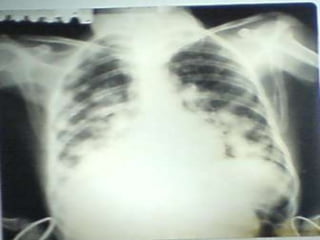

• C’est un téléthorax de face objectivant de multiples opacités de

tonalité hydrique de taille et de formes variables intéressant les

deux champs pulmonaires prédominant au niveau des bases,

confluentes par endroits de plage homogène.

• L’index cardio thoracique ne peut être mesurer, les culs de sacs

pleuraux sont libres et on note l’absence de lésions osseuses

visibles

• Conclusion : syndrome interstitiel et de comblement alvéolaire

réalisant l’aspect en lâché de ballon évoquant des localisations

secondaires.

• Diagnostic différentiel : staphylococcie pleuro pulmonaire

• CAT : TDM thoraco-abdominale, échographie abdomino-pelvienne

et scintigraphie osseuse .Ce bilan d’extension a un double

intérêt : celui de rechercher le néo primitif et celui d’essayer de

déterminer d’autres atteintes